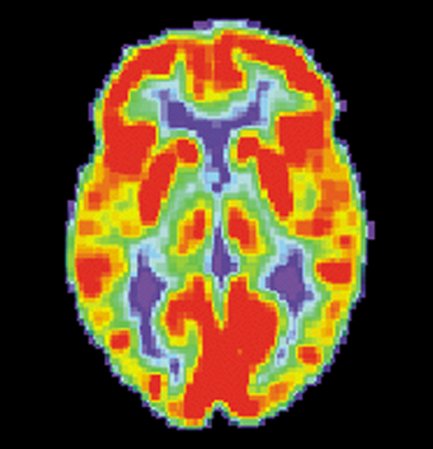

Research on brain implants has exploded in recent years. With the right mechanisms, they have the potential to help people with everything from paralysis and Parkinson’s disease to certain types of eye damage and blindness.

These implants, which are surgically inserted into the cortex of the brain, work by stimulating neurons that then target specific cells throughout the body. But until recently, many of these brain implants have been electrode-based, relying on conductivity between the metal plate, the implant, and the nerves around it. These devices often become less effective overtime, and the metal plates can (and often do) corrode. Their need for direct contact between the metal and the brain can lead to problems as well.